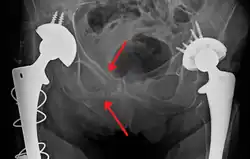

Fractures of the superior (in two places) and inferior pubic rami on the person's right, in a person who has had prior hip replacements

Pelvic fractures are most commonly described using one of two classification systems. The different forces on the pelvis result in different fractures. Sometimes they are determined based on stability or instability.[9]